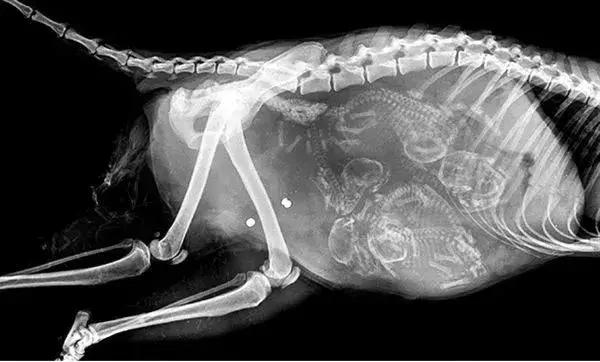

●建议照x光时间:超过8周才能确定小猫数量。

猫怀孕的外表徵状最早是乳头的颜色从淡粉红变为深粉红色,而且由于乳头旁的毛会脱落,使得乳头显得特别突出。这些症状应该在交配后3周内出现,受孕后3-4星期,是明显的圆球状。在这之后,胎儿反而不是这么容易摸出,但是也是可以触摸出来。如果有必要,在2-3周内也可以照超音波来看胎儿;怀孕后5周半可以照X光查看胎儿数目。

猫不像人类一样可以用验孕试纸来检查,因此早期的怀孕确认几乎是不可能的。母猫配种后21-28天,应带猫咪到宠物医院进行腹部触诊及超音波扫描,此时就可以确认是否怀孕了,并且可以估算出大概的胎数。超过46天后,就可以进行X光照影来确认胎数,及每两周进行一次超音波扫描来确认胎儿的状况,并可估算出大概的预产期。